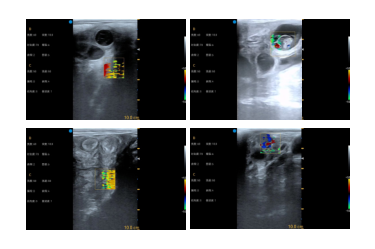

多普勒彩色超声系统Plus